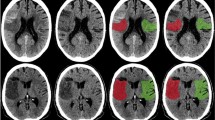

Association of variables with pCore overestimation

Following stratification, an association between age, ASPECTS, eTICI grade, pCore, and NWU and core overestimation was observed in the subgroup of patients with a pCore ≥ 50 mL, while NIHSS, pCore, and NWU were the only significant predictors of core overestimation in the small core (pCore < 50 mL) subgroup (Figs. 2 and 3, Supplementary Table S3).

Examples of patients with high (A–C) and low (D–F) NWU and their association with pCore overestimation. Both patients presented within a similar time frame and achieved near-completed reperfusion. (A, D: admission imaging; B, E: rCBF < 20% CTP maps; C, F: follow-up imaging). NWU net water uptake; pCore rCBF20%-defined core at admission; CTP CT perfusion.

The purpose of this study was to investigate the relationship between NWU on admission imaging and the probability of CTP-based ischemic core overestimation. We hypothesized that patients with large cores, yet low NWU were the most likely to show core overestimation. The main findings of this study are shown Fig. 2; in this patient cohort, low NWU was indeed significantly associated with core overestimation, thus supporting our hypothesis. Interestingly, this relationship appeared to be particularly robust for the subgroup of patients with large baseline ischemic cores. We also observed that patients with higher levels of NWU on admission imaging had increased lesion growth, although this relationship was no longer significant following adjustment for patient baseline characteristics and reperfusion status. Despite this, these data support a more granular depiction of lesion growth dynamics and propose a multi-stage chronological approach to ischemic core lesion imaging, based on known metabolic processes. Initially, the cells distal to the arterial occlusion undergo oxygen deprivation, resulting in a compensatory increase in CBF. Over time, however, these compensatory mechanisms fail, leading to a progressive decline in CBF and CBV, with transformation of the penumbra into irreversibly damaged tissue. Due to continued cellular oxygen deprivation, disruption of the blood brain barrier ensues, leading to the influx of ions and subsequently tissue water uptake. The combined assessment of CTP parameters and NWU could reflect these stages; in patients with large CBV deficits, but low NWU, the compensatory mechanisms are largely maintained–the core lesion is “reversible”. On the other hand, those with large CBV lesions and high NWU have more likely crossed the threshold into irreversible tissue damage. It is possible that these patients also experience more growth due to a developing increase of NWU within “borderline” penumbral tissue, signaling initial breakdown of the blood–brain-barrier, which was not assessed in this study. Furthermore, the current definition of core volume is based on binary thresholding, thereby likely oversimplifying complex pathophysiological processes17. It would be interesting, therefore, to examine whether there is a “gradient” of NWU around the CBV-derived core lesion.